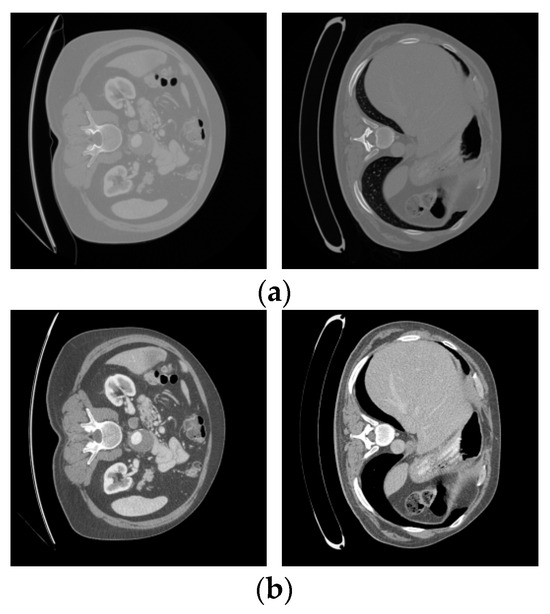

5.1. Dataset

5.2. Data Preprocessing

5.3. Experiments